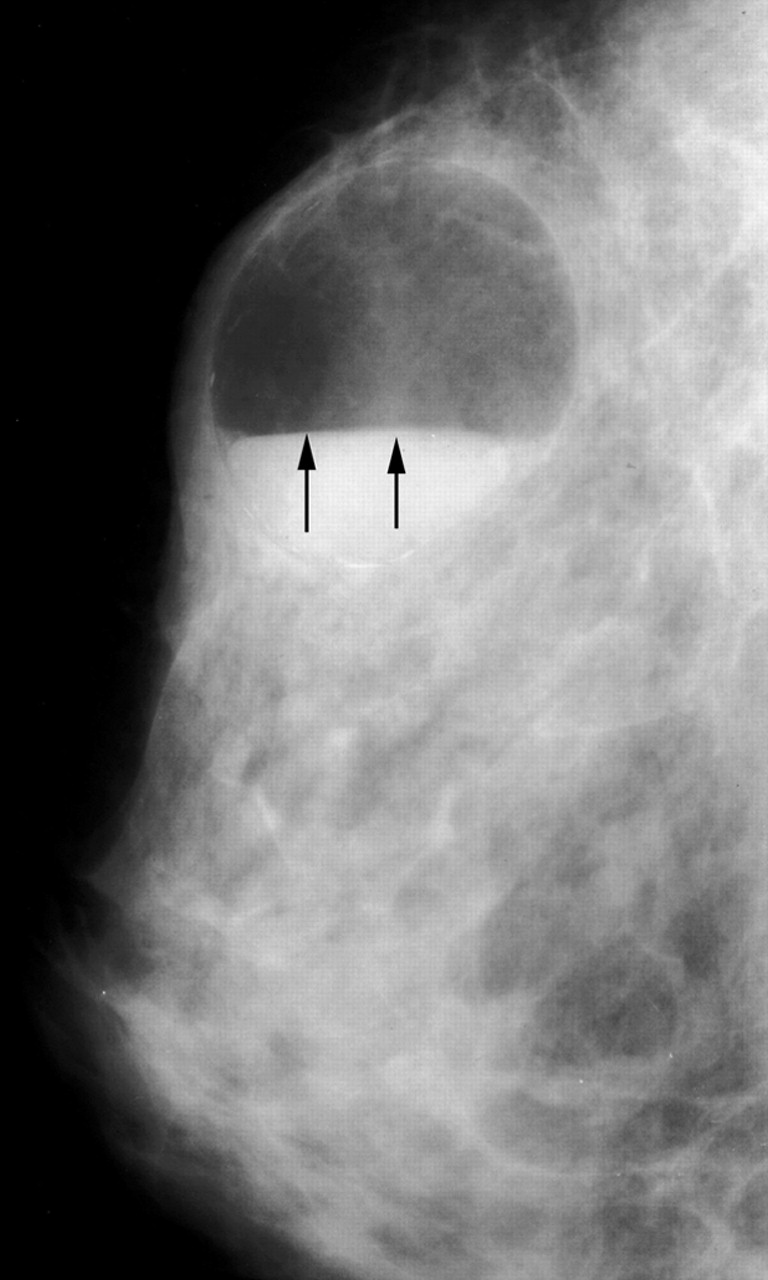

A

B

Cystic mass with fat-fluid level galactocele. (a) Mammogram reveals an oval circumscribed mass with the characteristic fat-fluid level (arrows). In this type of galactocele, the milk content is fresh and fluid, allowing the fat to rise and the heavier water content to remain in the lower portion of the cyst. (b) US image also demonstrates the fat-fluid level (long arrows), with typical high and low echogenicity. Note that the fatty component has risen and occupies the upper (nondependent) portion of the cyst, whereas the heavier water content remains in the lower (dependent) portion. Note also the clot of fatty milk (“cream”) (short arrow) floating in the nondependent portion of the cyst owing to its intermediate density.